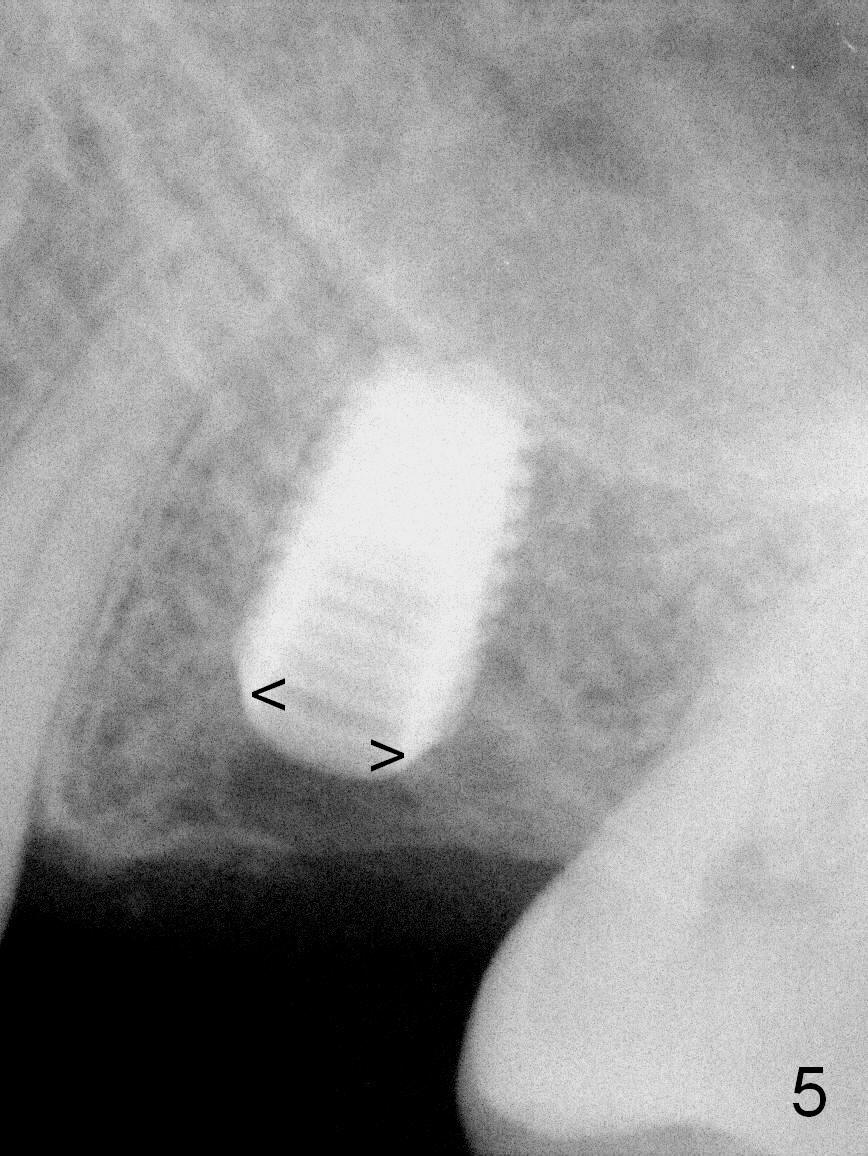

A 49-year-old man is an engineer. The tooth #14 is missing (Fig.1,2). He wonders how a one-rooted implant can replace a three-rooted tooth. Anyway, osteotomy is initiated at the site with 2.5 mm reamer in place (Fig.3). A 5x8 mm Bicon implant is placed (Fig.4). Seven and a half months later, the bone density next to the implant plateau appears to increase (Fig.5 arrowheads, as compared to Fig.4). The beauty of Bicon implant is that the crown (Fig.6 C) can be extraorally cemented to the abutment (A) prior to re-seating. Two years and 3 months post cementation, while no residual cement is visible, the bone density at the crest has increased (Fig.7 arrowheads). The crown is de-cemented 4 years 4 months post cementation; it appears that the abutment is small and short (5x2 mm 10 degree stealth). The bone density of the cortex around the implant (Fig.9 ^) is higher than that at #15 and #3.